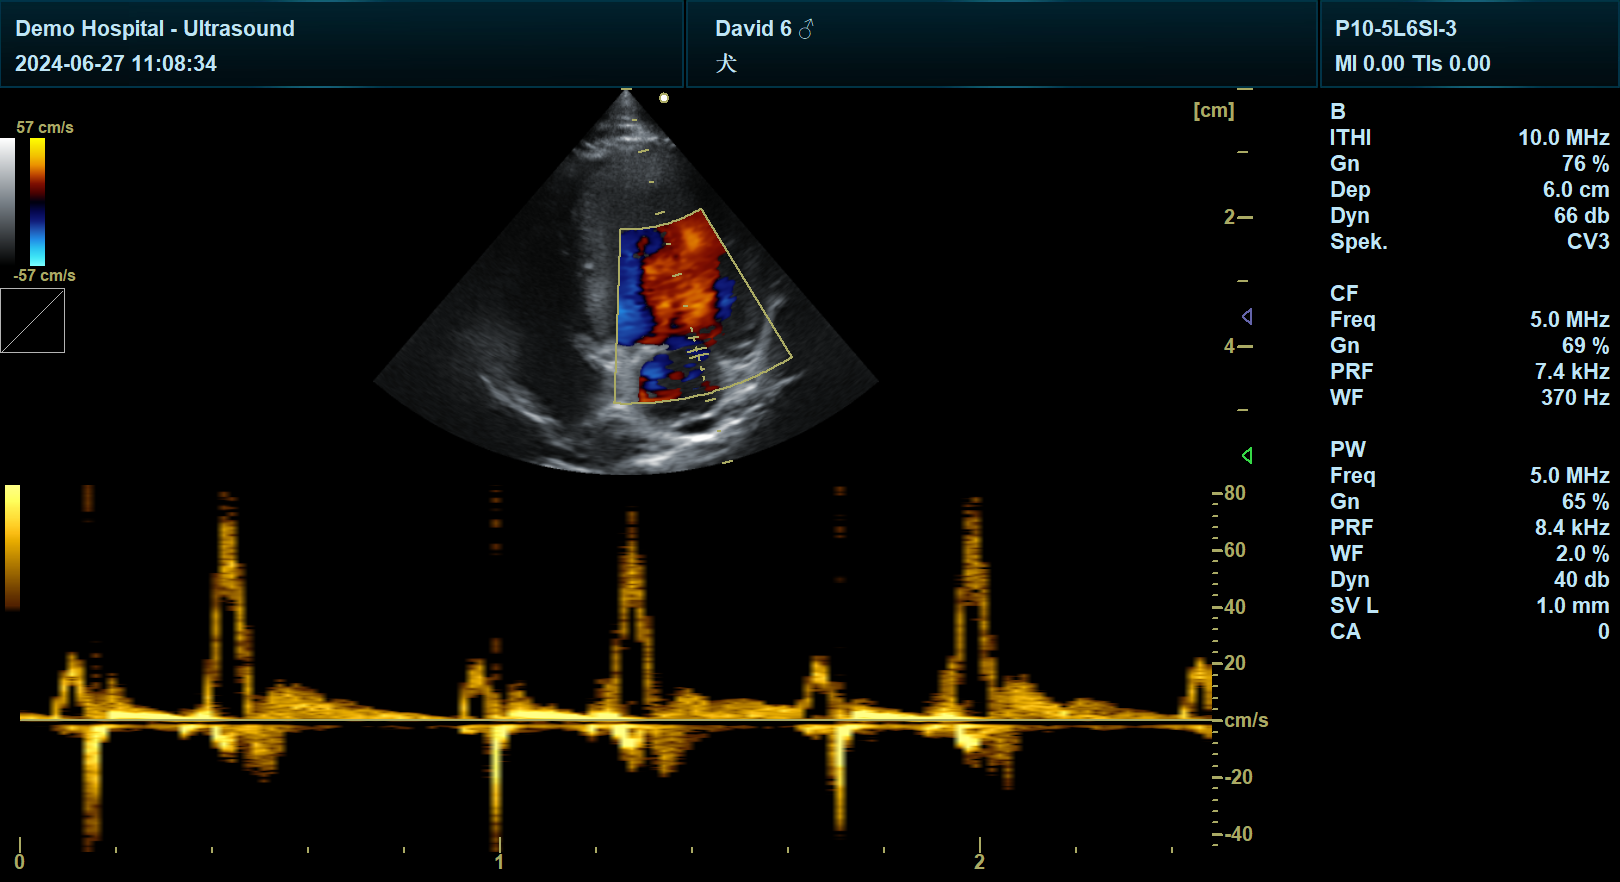

多普勒模式应用:

彩色多普勒:观察房室瓣反流及湍流,评估瓣膜功能。

脉冲多普勒(PW)或连续多普勒(CW):测量二尖瓣E峰(心室舒张期流速)和A峰(心房收缩期流速)。

犬:E峰<1.05m/s,A峰<0.64m/s为正常。